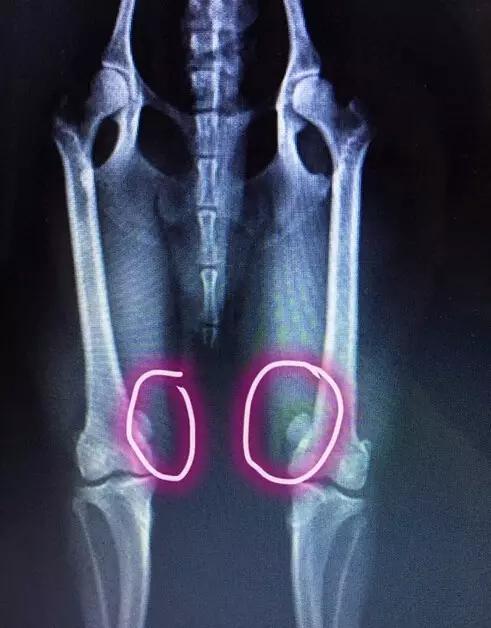

主人心急带奔奔去医院拍片检查,结果是髌骨脱臼。

简单来说~其实髌骨就是膝盖骨,在大腿的四头肌头下~通常髌骨在骨关节的凹槽中,但是如果狗狗经常做一些违反“狗体原理”的动作,髌骨会脱出这个凹槽。

而且不及时治疗,它会造成胫骨和骨骨骼变形,甚至会导致狗狗下半身瘫痪。